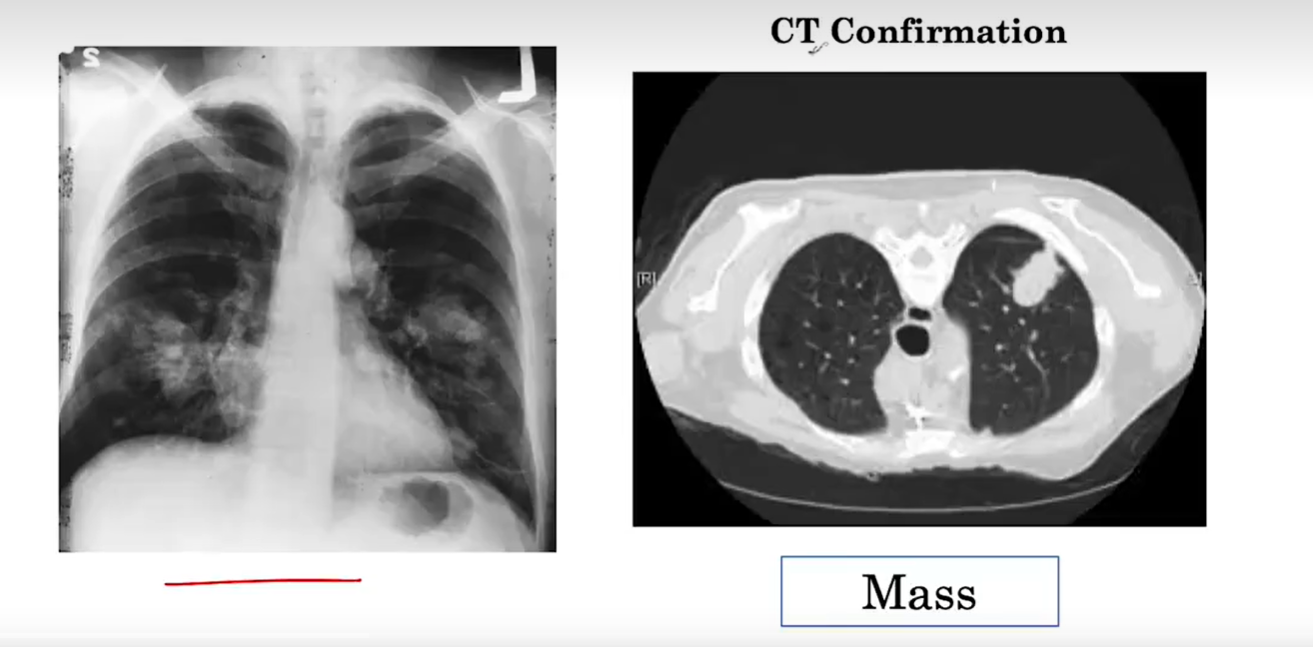

[技术交流] 2. 医学人工智能—判断X胸片中是否有肿块【模型训练及评估】

下载 (67).png